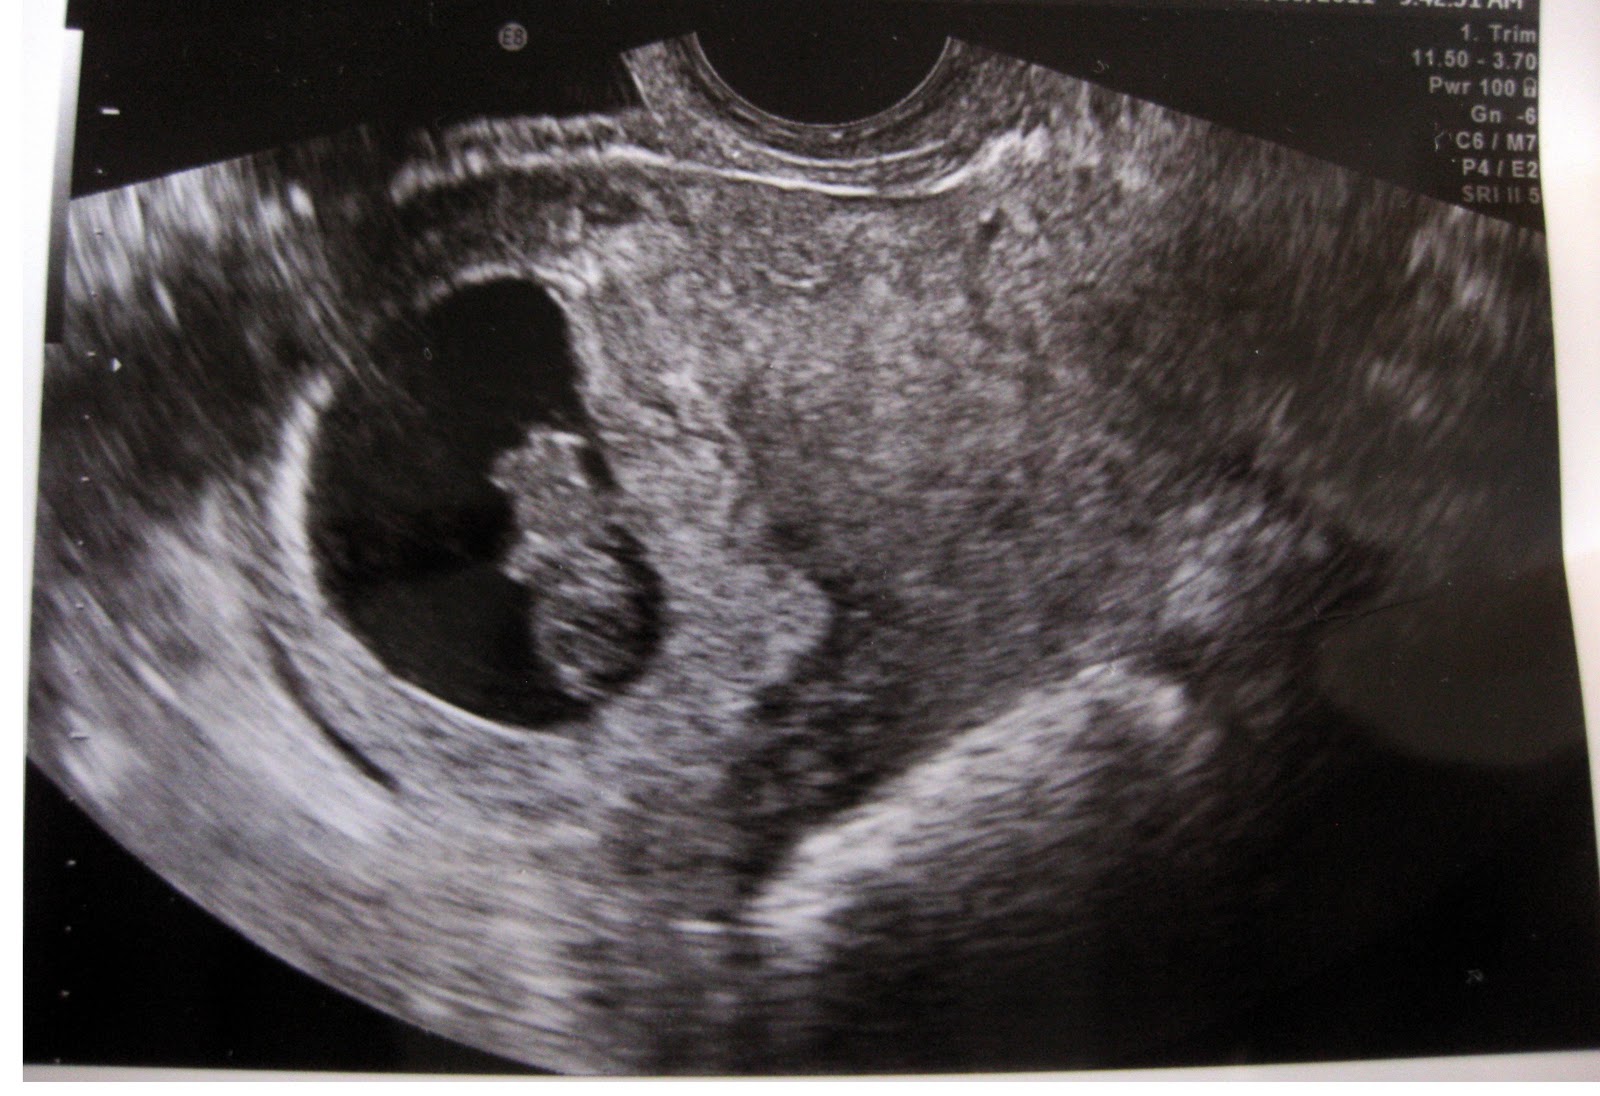

Фото Плода 7 8 НедельВЫБЕРИТЕ ВАШ ПОЛ👨 👉🏻👉🏻👉🏻МУЖЧИНА👈🏻👈🏻👈🏻👩🦱 👉🏻👉🏻👉🏻ЖЕНЩИНА👈🏻👈🏻👈🏻Фото Плода 7 8 Недель (263 фото)<